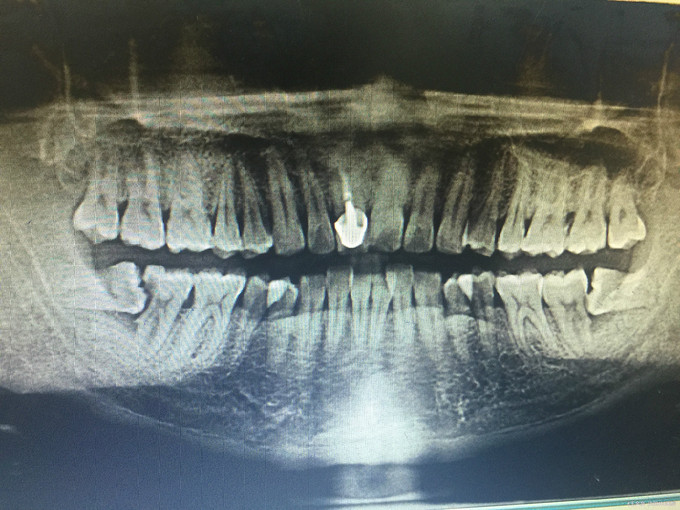

临床检查:47远中龋坏,探疼(+),冷(++),叩(-),松动度(-),牙周正常. 48未完全萌出, 辅助检查:X线示47远中龋坏累积髓腔,48近中水平阻生。

诊断:47牙髓炎,48阻生齿 治疗:经患者知情同意后,48拔除,47局麻去腐降牙合,开髓拔髓寻找根管口,建立直线通路,扩通根管,确定工作长度。S3/EDTA凝胶镍钛器械,低浓度次氯酸钠冲洗根管,预备至35/04,氢氧化钙诊间封药,一周后复诊,试主尖X线示恰充,试干根管,导AH-PLUS糊剂,VDW热压胶垂直加压根充,术后见根管恰充,暂封调合抛光。观察桩冠修复。